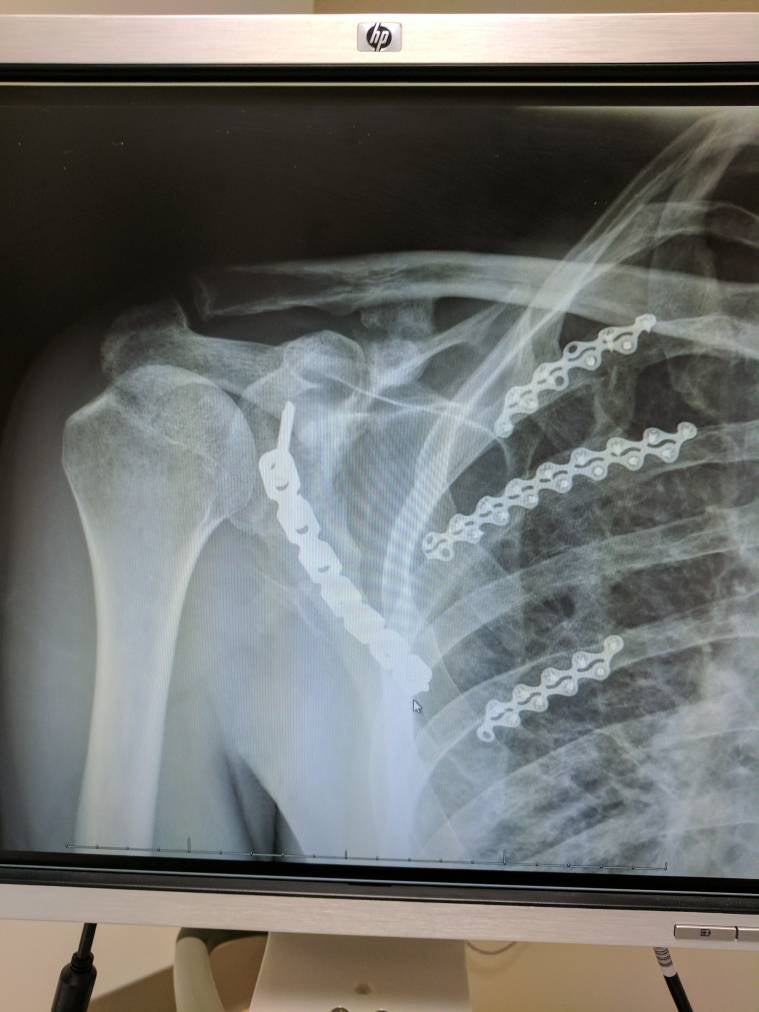

Rough trip Scapula fracture Radiology Key

From radiologykey.com

From www.reddit.com

Fractured scapula from bike crash r/Radiology Broken Scapula Mtb It might hurt, but if a broken collarbone is the worst of your injuries, you have a lot going for you. Learn about the most common mountain biking injuries, such as shoulder, ankle and wrist breaks, dislocations and ligament damage, and how to recover from them. I thought i had dislocated it again but it turns out that i had. Broken Scapula Mtb.

Fractured scapula from bike crash r/Radiology Broken Scapula Mtb If you’re breathing and your legs still work, you may be. It feels really uncomfortable and hard to move. This injury typically occurs when the rider falls or flips over their handlebars, driving their shoulder into the ground or falling onto an outstretched hand. From hitting a pine tree, shoulder first, and. Broken my scaphoid bone on my weak hand. Broken Scapula Mtb.